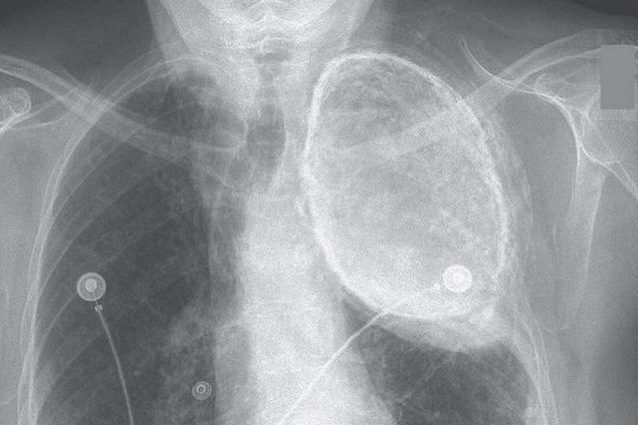

[didascalia fornitore=”foto”]di The New England Medical Journal[/didascalia]

Per oltre 60 anni ha vissuto con un polmone completamente immerso nell’olio, ma l’ha scoperto solo quando si è sottoposta a una visita specialistica per sospetta angina. L’anziana signora di 86 anni, molti anni prima, si era sottoposta a un trattamento per contrastare la tubercolosi polmonare. In pratica, il liquido impiegato nella tecnica, ossia un olio vegetale, non le è stato mai rimosso, come invece imponeva il protocollo. Fortunatamente per lei non ha mai sviluppato complicanze o infezioni dalla presenza di questo elemento estraneo iniettato nel suo corpo. Ma si è accorta della sua presenza solo dalla radiografia fatta per i controlli alle coronarie.

In cosa consisteva tale tecnica anti tubercolosi? Semplice, tramite una infusione veniva riempita di olio l’intera cavità pleurica, ossia quella porzione di spazio che si trova tra la pleura viscerale e la membrana che avvolge i polmoni.

La prassi dell’oleotorace voleva che, dopo un periodo di massimo due anni, l’olio venisse eliminato dai corpi dei pazienti, aspirato fino all’ultima goccia per impedire possibili infezioni.